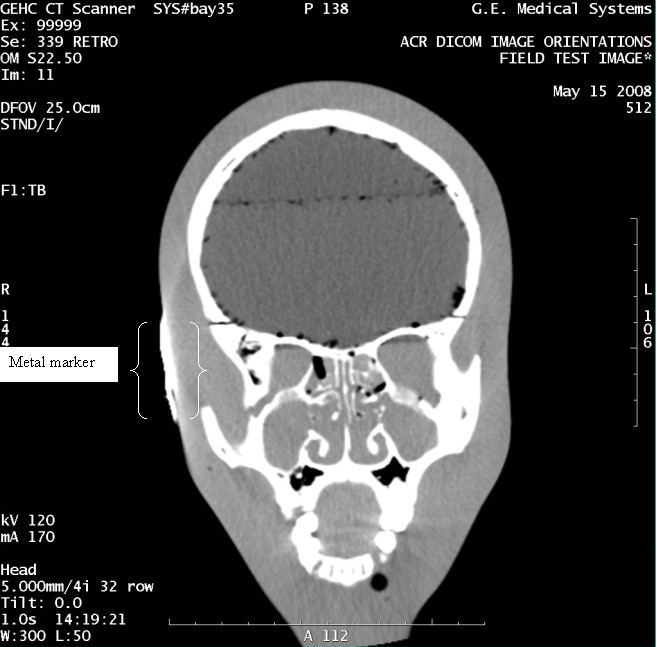

- With the support of the site personnel, examine the images sent

to the Review Station (i.e., 12 series, each with 1 image) and compare

their orientation to the images in this document.

- Each image contains a metal marker on the phantom's right cheek.

- Each image in this document contains a description of the expected

orientation of the metal marker (i.e. to prove Left and Right) as

well as the Posterior and Anterior orientation description.note:

The sample images included in this document use “R”, “L”, “P”, and “A” for “Right”, “Left”, “Posterior” and “Anterior” orientation. The Hospital Review Station may use a different style of annotation. The style used is not relevant to this procedure.

Figure 9. Exam 99999, Series 339